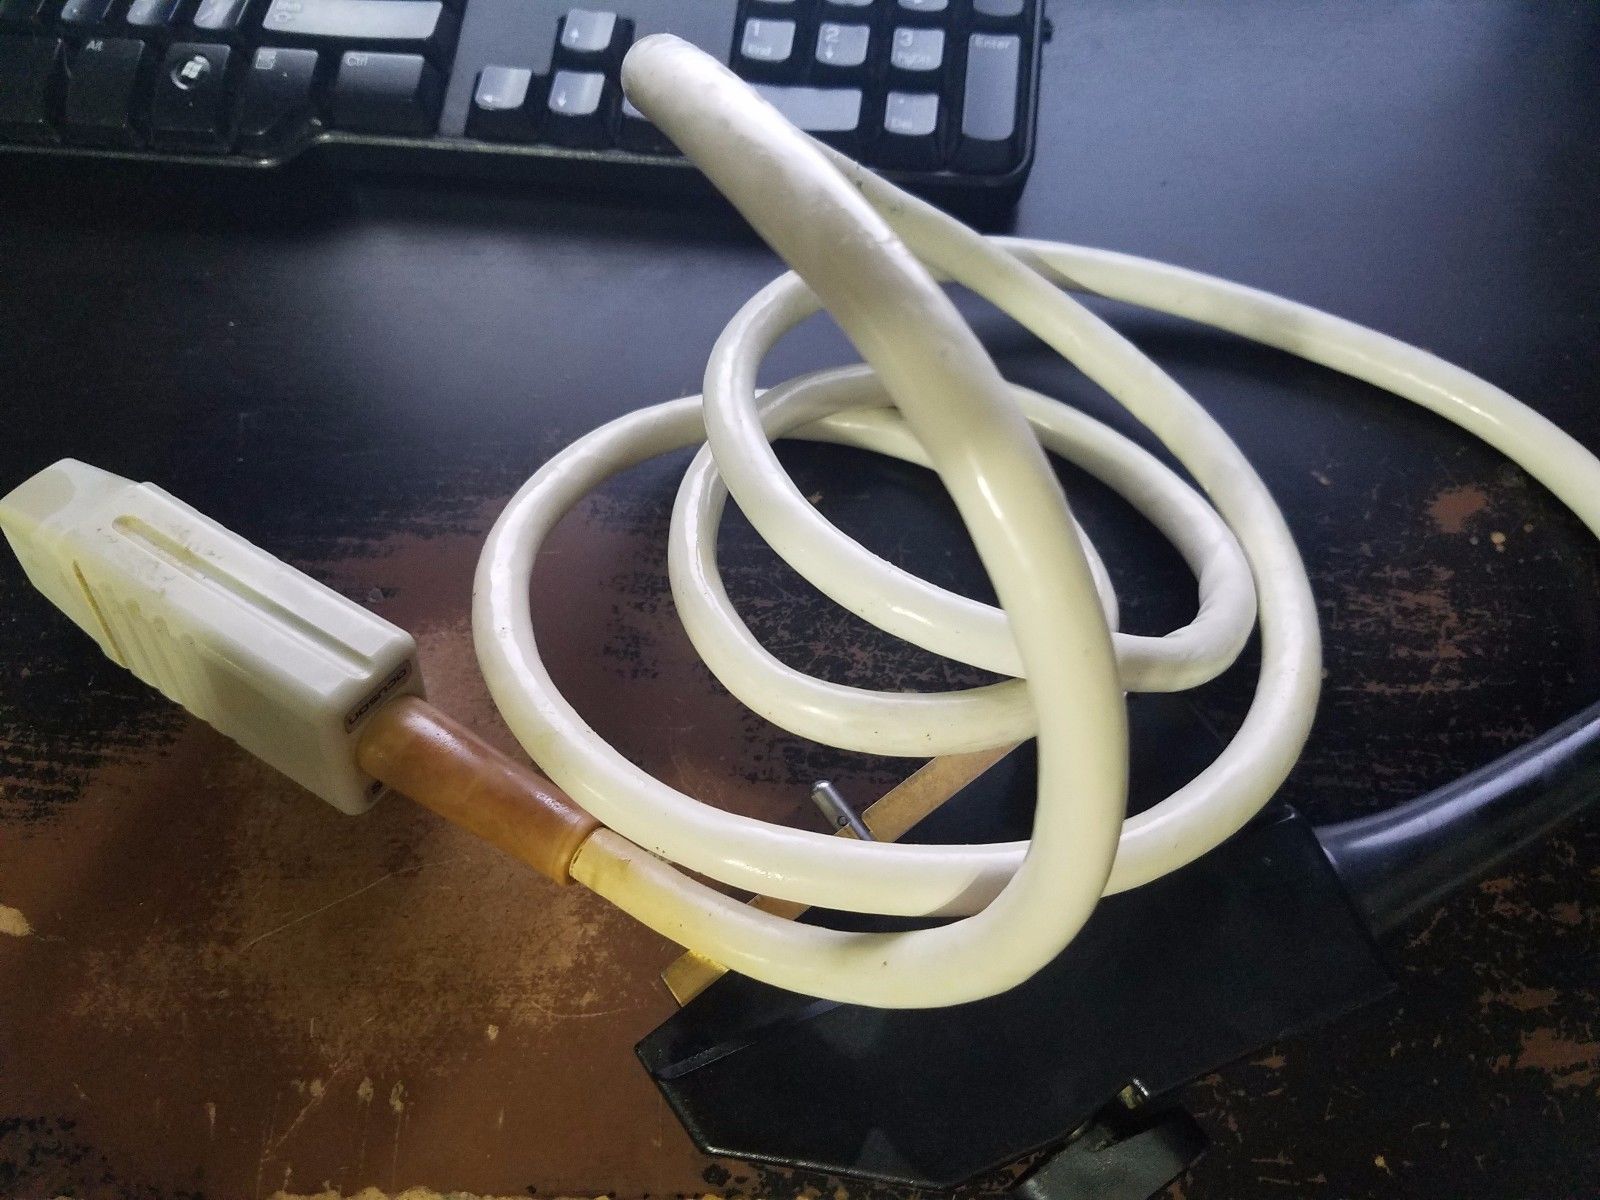

Acuson Linear Ultrasound Probe 7L3 08267217